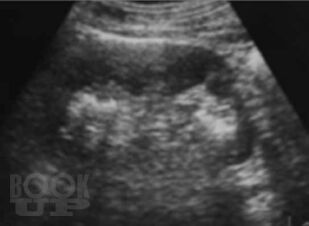

Настоящая монография предназначена для врачей – лучевых диагностов, урологов, хирургов, терапевтов, семейных врачей, а также студентов медицинских вузов, и посвящена применению лучевых методов исследования в диагностике различных форм острого гнойного пиелонефрита.

В монографии детально показана разнообразная лучевая семиотика при апостематозном пиелонефрите, карбункуле и абсцессе почки, а также представлены различные современные методы лечения с динамикой воспалительных изменений в паренхиме почки.